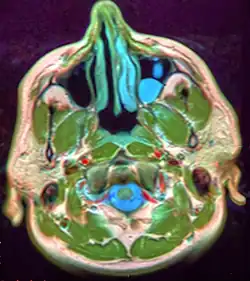

Mucous extravasation phenomenon is a swelling of connective tissue consisting of a collection of fluid called mucus. This occurs because of a ruptured salivary gland duct usually caused by local trauma (damage) in the case of mucous extravasation phenomenon and an obstructed or ruptured salivary duct in the case of a mucus retention cyst. The mucocele has a bluish, translucent color, and is more commonly found in children and young adults.

The size of oral mucoceles vary from 1 mm to several centimeters and they usually are slightly transparent with a blue tinge. On palpation, mucoceles may appear fluctuant, but can also be firm. Their duration lasts from days to years,[4] and may have recurrent swelling with occasional rupturing of its contents.

Microscopically, mucoceles appears as granulation tissue surrounding mucin. Since inflammation occurs concurrently, neutrophils and foamy histiocytes usually are present. On a CT scan, a mucocele is fairly homogenous, with an attenuation of about 10-18 Hounsfield units.[5]